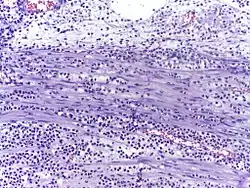

Micrograph showing several neutrophils during an acute inflammation

Low neutrophil counts are termed neutropenia. This can be congenital (developed at or before birth) or it can develop later, as in the case of aplastic anemia or some kinds of leukemia. It can also be a side-effect of medication, most prominently chemotherapy. Neutropenia makes an individual highly susceptible to infections. It can also be the result of colonization by intracellular neutrophilic parasites.